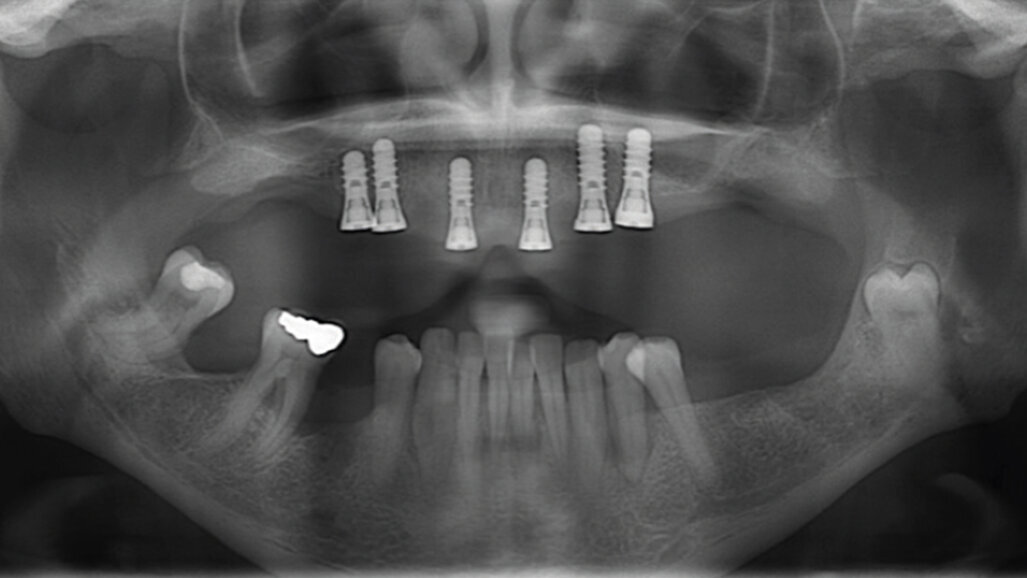

První část (tj. fáze před ošetřením) má za cíl perfektně připravit pacienta na samotné zavedení implantátu na základě vyhodnocení všech potenciálních rizikových faktorů, především se zaměřením na ten nejvýznamnější: zajištění stabilní parodontální situace (obr. 2).

Obr. 2: Před zaváděním implantátu by měla být zajištěna stabilní parodontální situace. Pacient před parodontologickým ošetřením (a), po parodontologickém ošetření a zavedení implantátu (b) a po nasazení protetické náhrady (c).